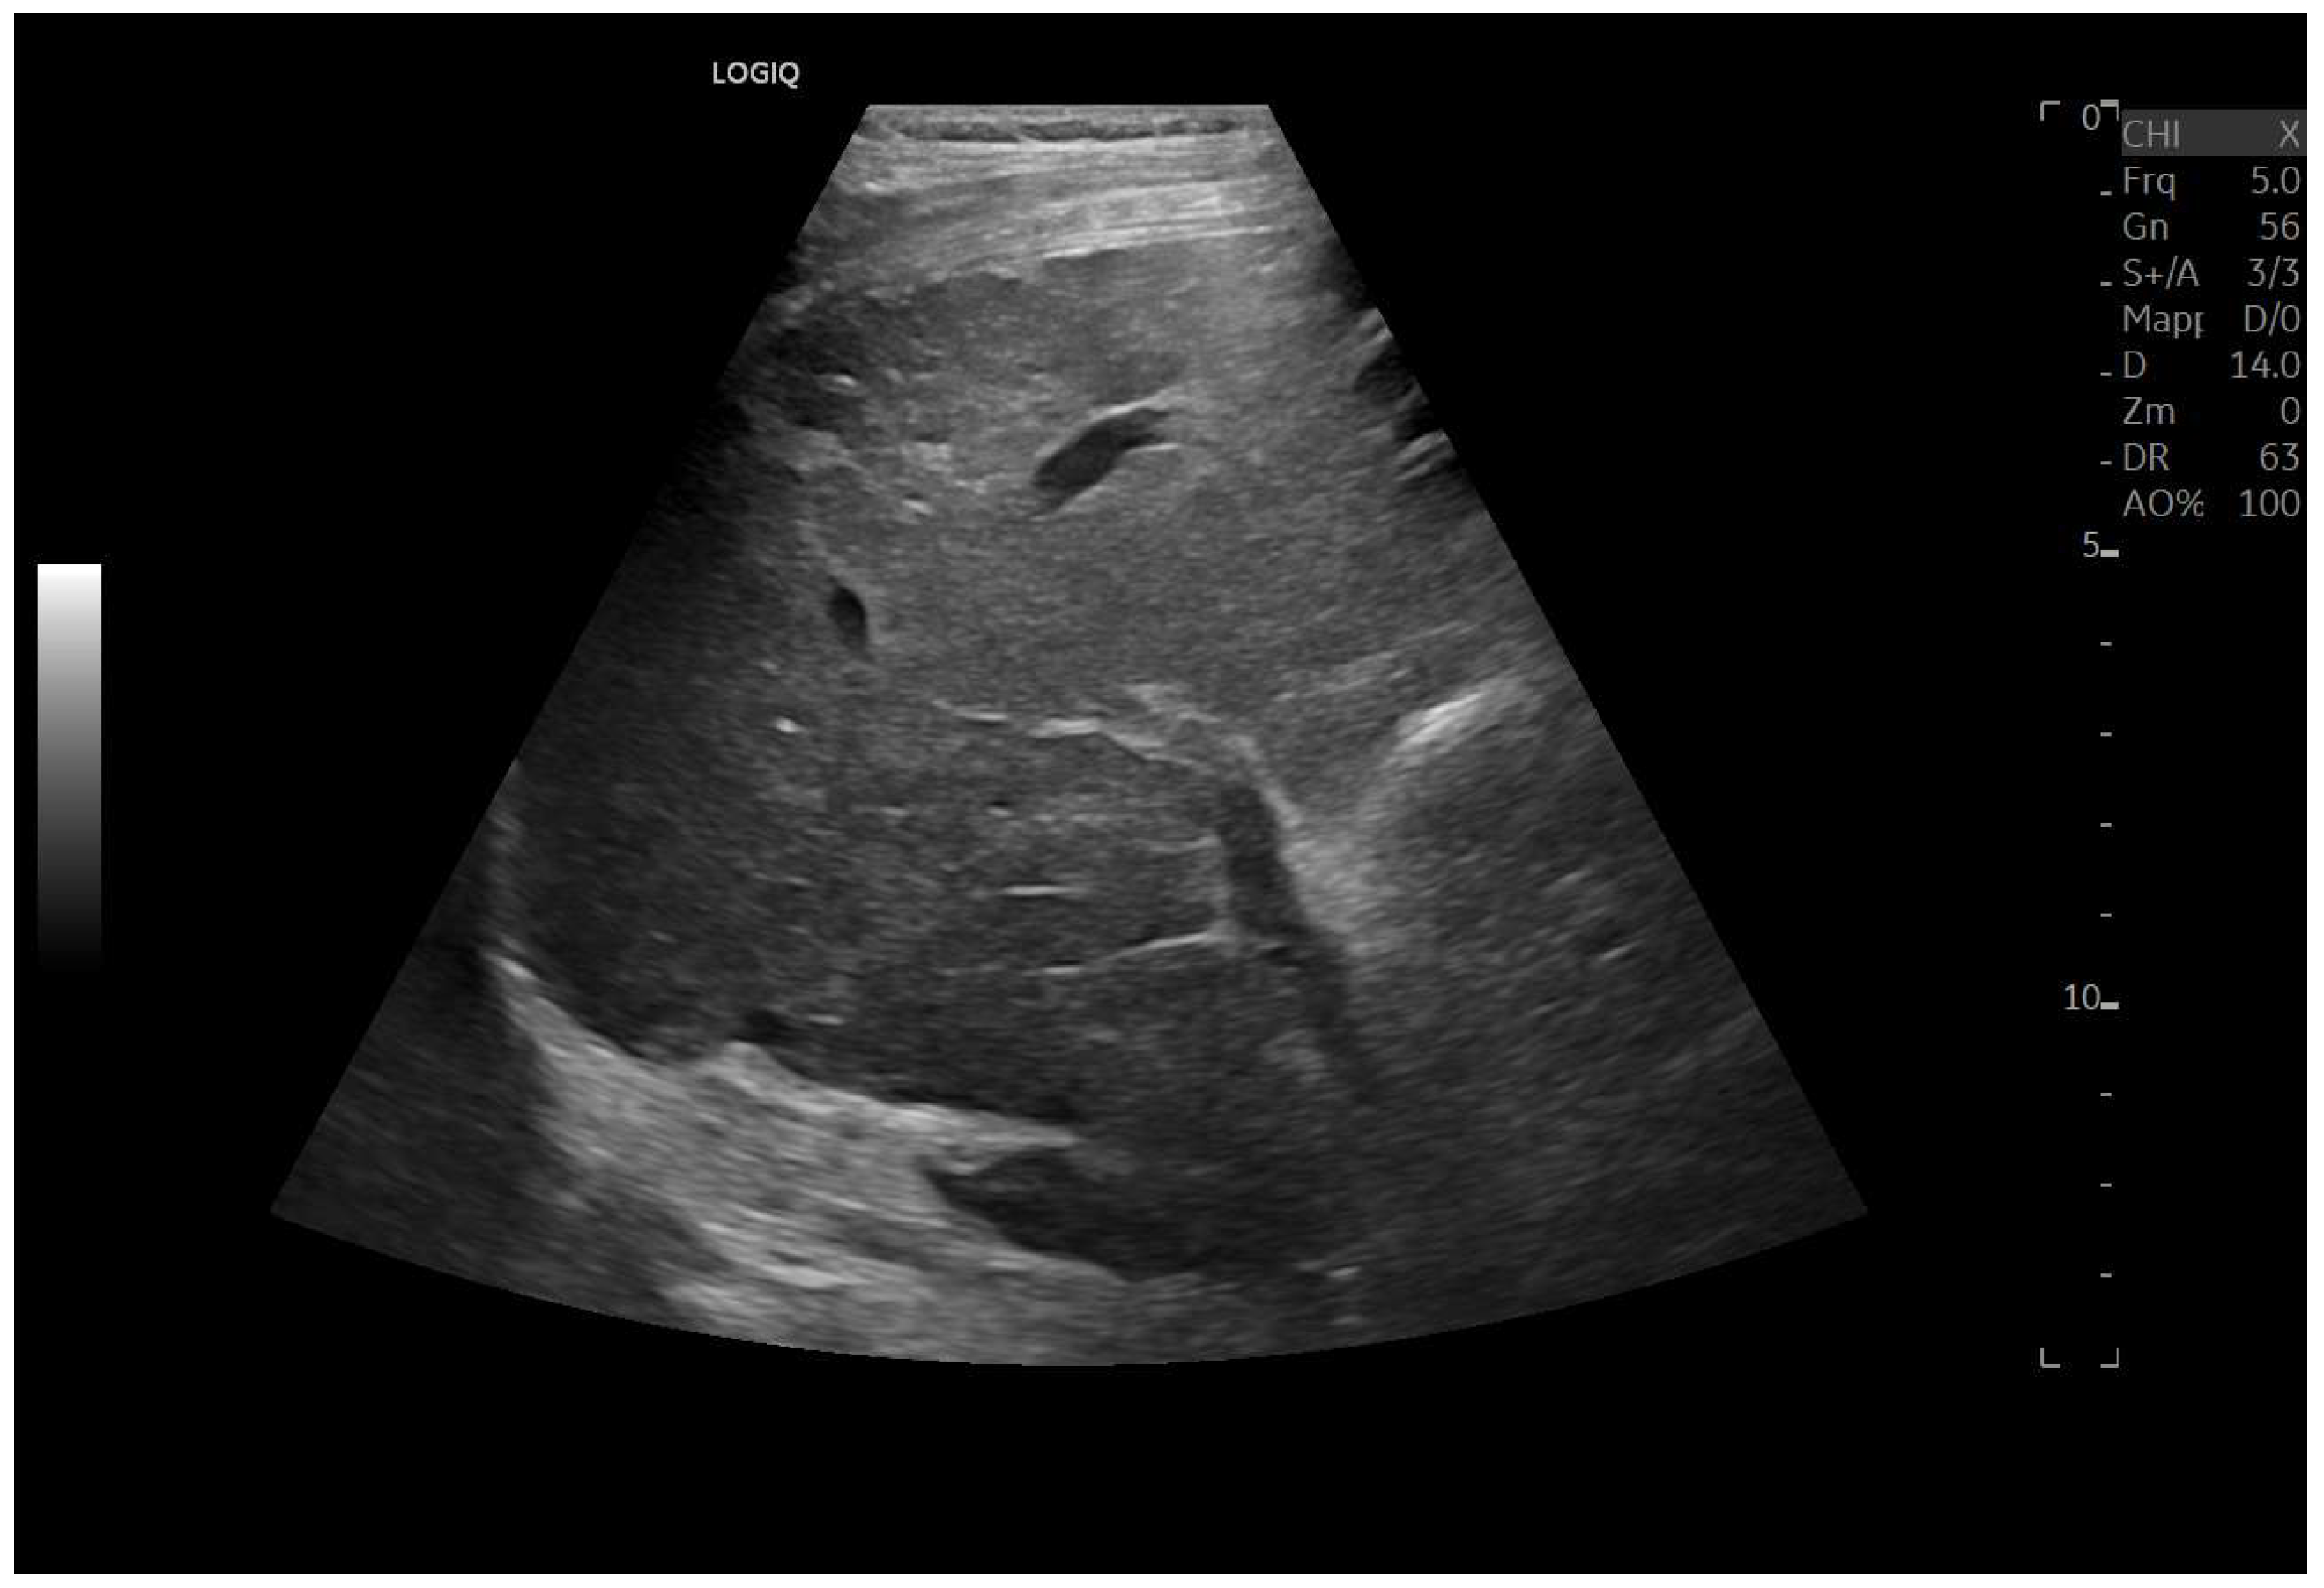

Figure 8.

Marked hypertrophy of the left lobe, which partially occupies the left hypochondrium.